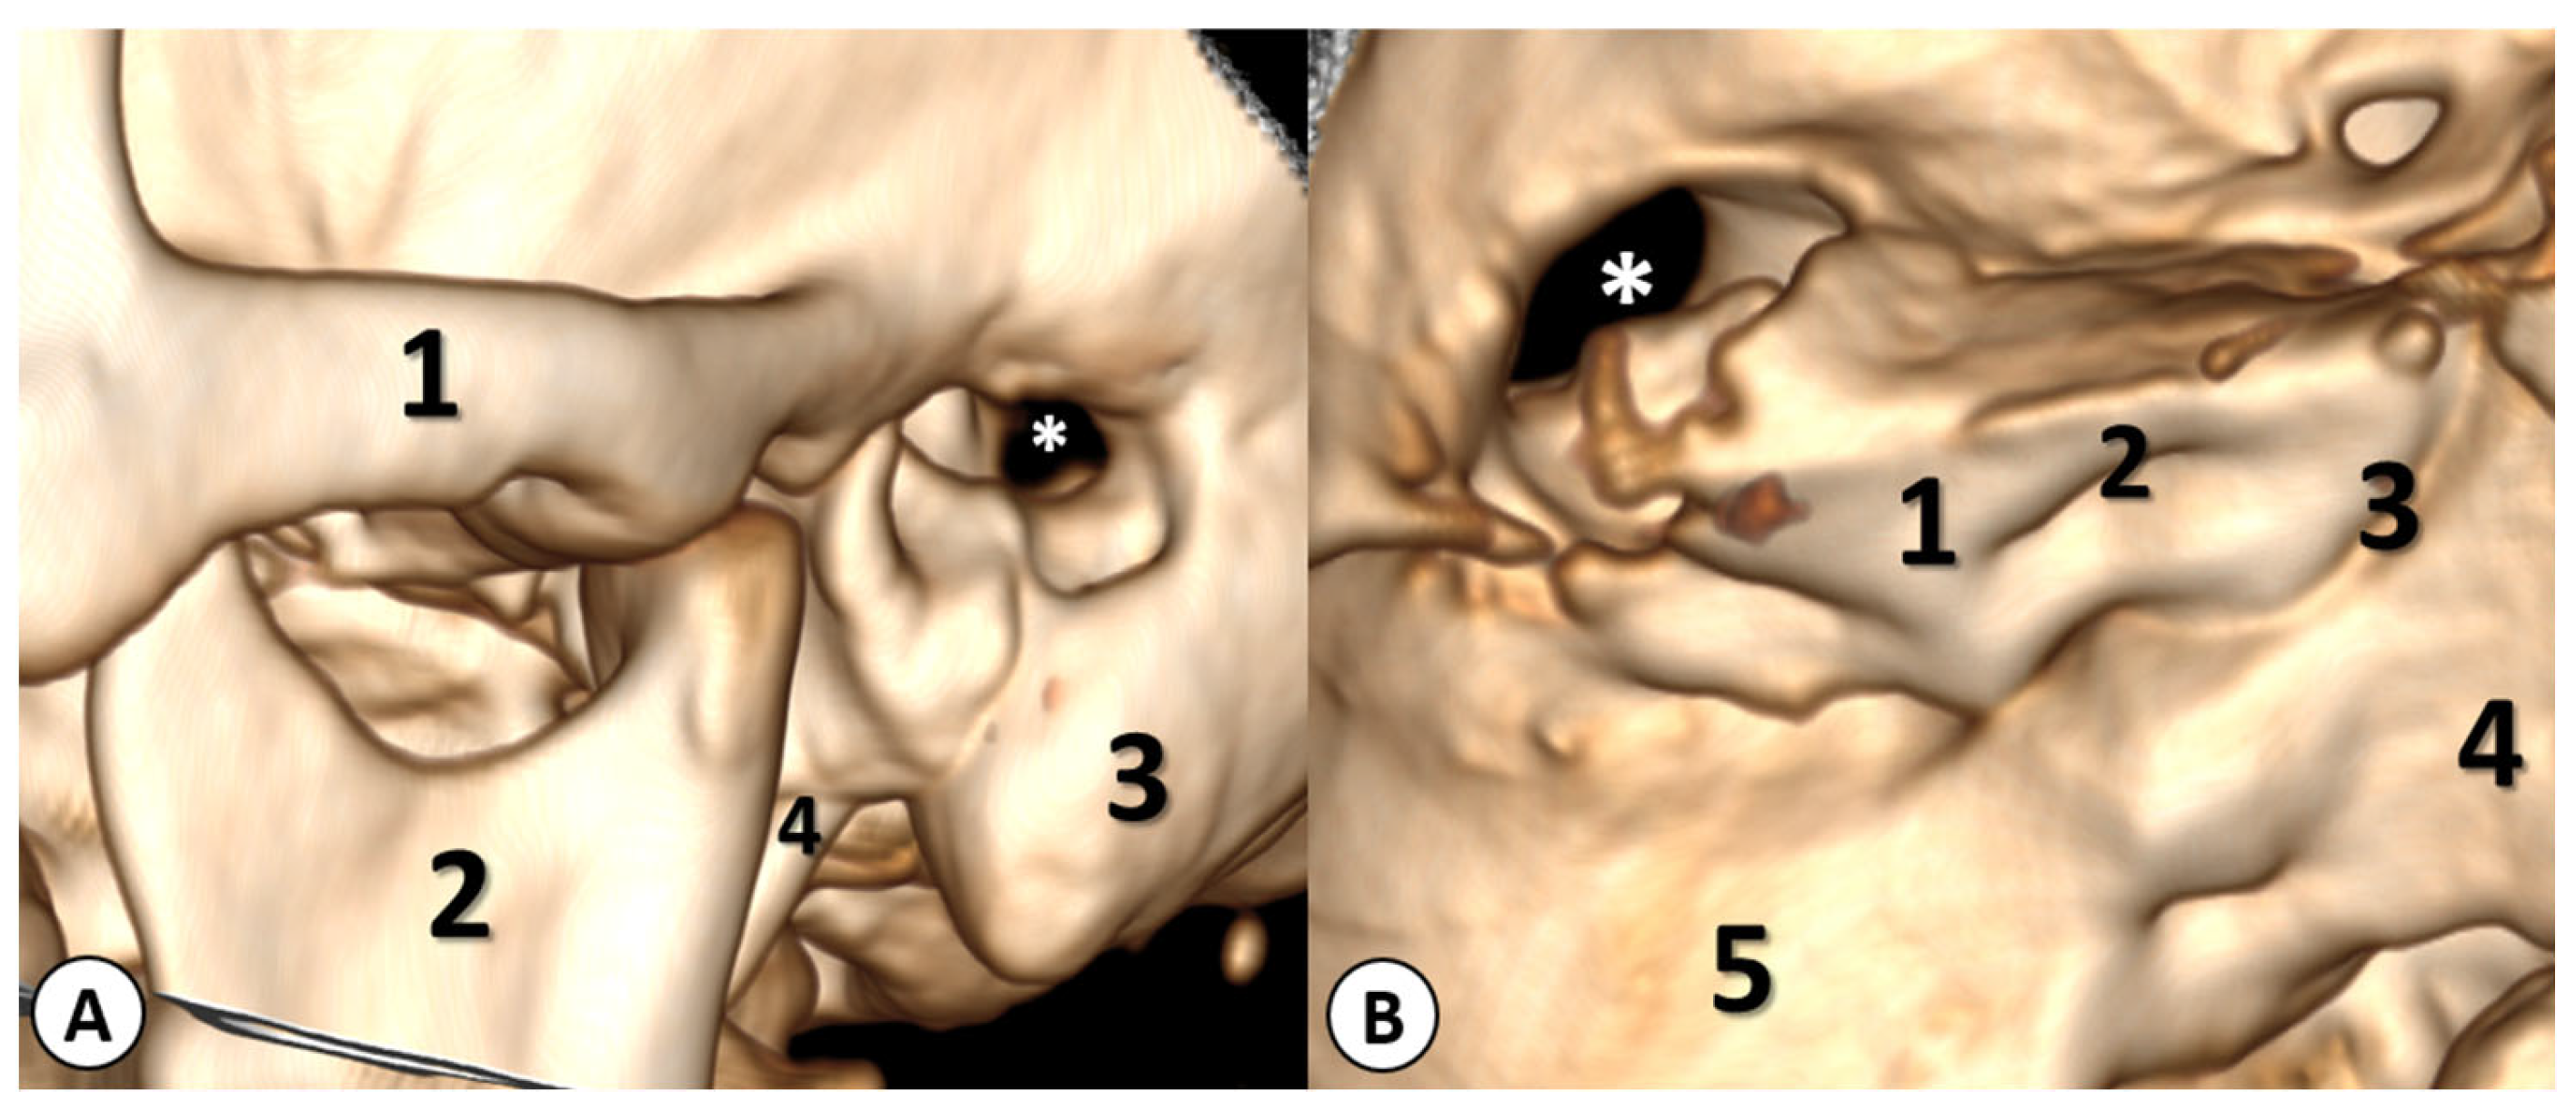

The computed tomography (CT) scan of the head revealed a left cholesteatomatous otomastoiditis (Figure 1A) and a lesion in the left cerebellar hemisphere, which appeared to have continuity with the cavity from the left mastoid (Figure 1B).

Figure 1. (A): Axial CT scan showing a left cholesteatomatous otomastoiditis. In the left ear, you can observe widening of the aditus [A] and the formation of a common cavity between the epitympanum [E] and the aditus with soft tissue within. In the right ear, normal anatomical structures can be seen: the epitympanum, aditus ad antrum, and mastoid antrum. (B) Axial head CT scan showing a well-defined hypodense lesion located in the left cerebellar hemisphere (red arrow). Moreover, in the bone window, erosion of the bony wall of the temporal bone can be observed, indicating a continuity between the left cholesteatomatous otomastoiditis and the posterior fossa (yellow arrow).